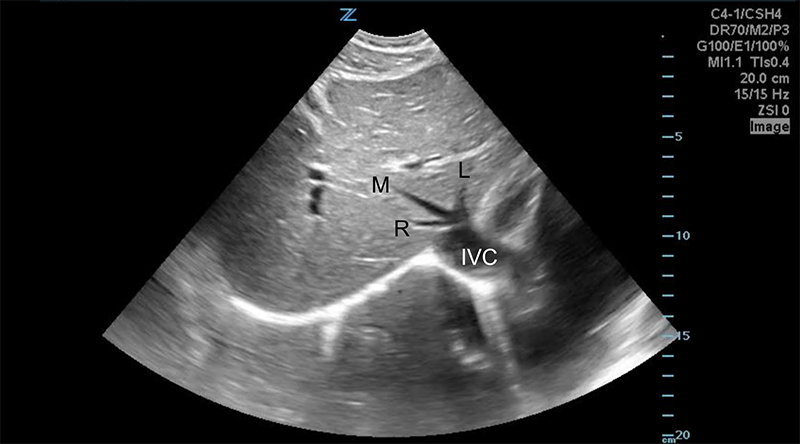

Figure 7. Transverse subxiphoid view of the liver. The middle hepatic vein divides the left and right lobes of the liver. The caudate lobe is located posterior to the left lobe. (R,M,L = Right, Middle, Left hepatic veins, respectively. IVC = Inferior Vena Cava)

Figure 8. Transverse subxiphoid view of the liver. Hepatic veins (orange arrows) are straight with thin walls, whereas portal veins (blue arrows) have bright walls and are more tortuous.